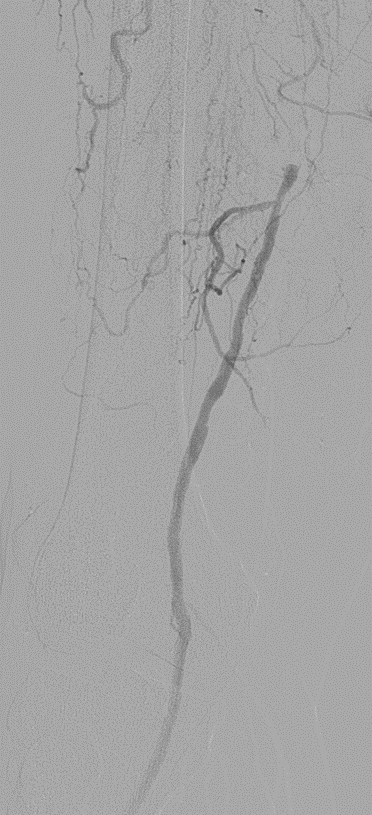

★ Case 1

noproximal stump in SFA,>250mm